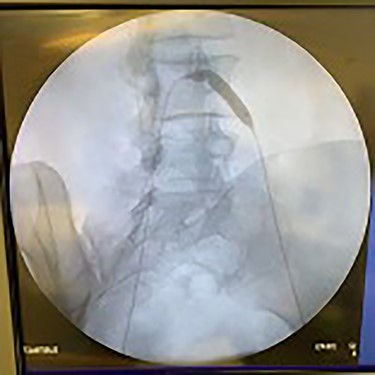

Catheter arteriogram results showed significant occlusion of the left iliac artery (Figs 3 and 4), the right iliac artery (Fig. 1), as well as the distal abdominal aorta (Fig. 2). There were numerous collateral vessels noted, indicating the presence of long-standing proximal stenosis (Fig. 1). The decision was made to use angioplasty to help widen the areas of stenosis. An 8 mm × 40 mm Passeo balloon was advanced from the right femoral artery into the left iliac artery (Fig. 7) and insufflated to 6 mmHg (Fig. 6). The balloon was allowed to remain expanded for 1 min and then was deflated. Next, the distal aorta was repaired in a similar fashion. The balloon was advanced into the distal aorta from the right femoral access and insufflated to 12 mmHg (Fig. 8). The balloon was allowed to remain expanded for 90 s.

Fluoroscopy of right iliac artery showing vast collateral vascular formation, indicating long-standing proximal obstruction.